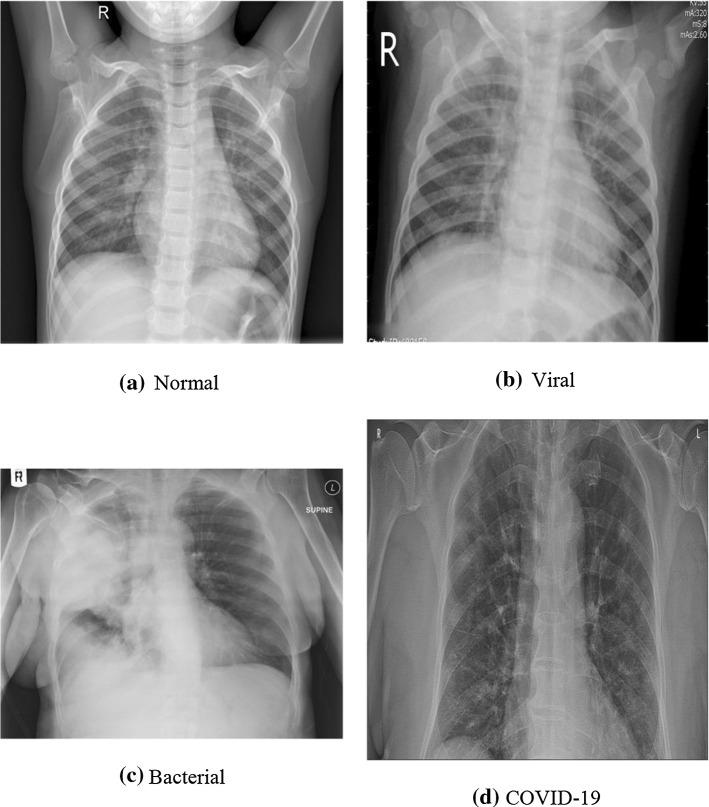

Putting real-time medical data processing applications into practice comes with some challenges such as scalability and performance. Processing medical images from different collaborators is an example of such applications, in which chest X-ray data are processed to extract knowledge. It is not easy to process data and get the required information in real time using central processing techniques when data get very large in size. In this paper, real-time data are filtered and forwarded to the right processing node by using the proposed topic-based hierarchical publish/subscribe messaging middleware in the distributed scalable network of collaborating computation nodes instead of classical approaches of centralized computation. This enables processing streaming medical data in near real time and makes a warning system possible. End users have the capability of filtering/searching. The returned search results can be images (COVID-19 or non-COVID-19) and their meta-data are gender and age. Here, COVID-19 is detected using a novel capsule network-based model from chest X-ray images. This middleware allows for a smaller search space as well as shorter times for obtaining search results.

将实时医疗数据处理应用付诸实践面临一些挑战,如可扩展性和性能。处理来自不同协作者的医学图像就是这类应用的一个例子,其中对胸部X光数据进行处理以提取知识。当数据量变得非常大时,使用中央处理技术实时处理数据并获取所需信息并非易事。在本文中,通过在协作计算节点的分布式可扩展网络中使用所提出的基于主题的分层发布/订阅消息中间件,实时数据被过滤并转发到正确的处理节点,而不是采用集中式计算的传统方法。这使得能够近乎实时地处理流式医疗数据,并使预警系统成为可能。终端用户具备过滤/搜索能力。返回的搜索结果可以是图像(新冠病毒感染或非新冠病毒感染),其元数据为性别和年龄。在此,使用基于新型胶囊网络的模型从胸部X光图像中检测新冠病毒感染。这种中间件允许有更小的搜索空间以及更短的获取搜索结果的时间。